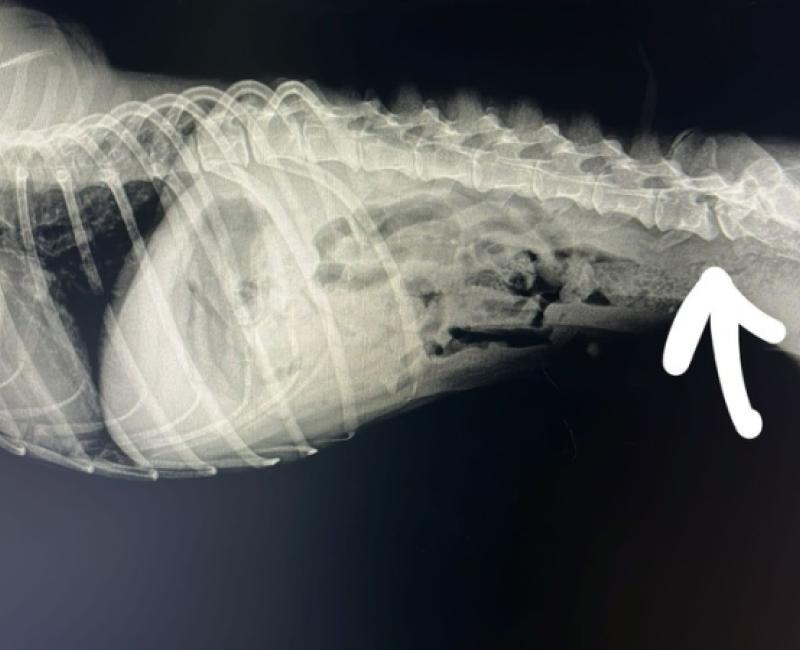

En este estado tan lamentable se encontró a LOLA BUNNY, posiblemente consecuencia de un atropello. Aparte del ojo como se aprecia en la foto, en el otro apenas tiene visión, un estado de anorexia bastante grave y, probablemente sufriría una lesión en la médula espinar que ha derivado en una marcha espinal, seguramente después de mucho tiempo y tras sufrir enormes dolores.